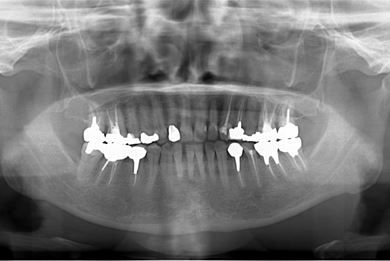

| 性別/年齢 | 女性 / 51歳 | ||||||||||||||||||||||||||||||||

| 主訴 | 前の歯の治療後の変色が気になる。詰め物がとれた箇所あり。痛みあり。 | ||||||||||||||||||||||||||||||||

| 治療方針 | セラミック治療にて、審美的回復を行う。 | ||||||||||||||||||||||||||||||||

| 治療内容 | オールセラミッククラウン7本(オールセラミック用土台1本)、ハイブリッドセラミッククラウン10本(ハイブリッドセラミック用土台9本)、ハイブリッドセラミックインレー1本 | ||||||||||||||||||||||||||||||||

| 総治療費 | 961,800円 | ||||||||||||||||||||||||||||||||

| 治療期間 | 10ヶ月 |